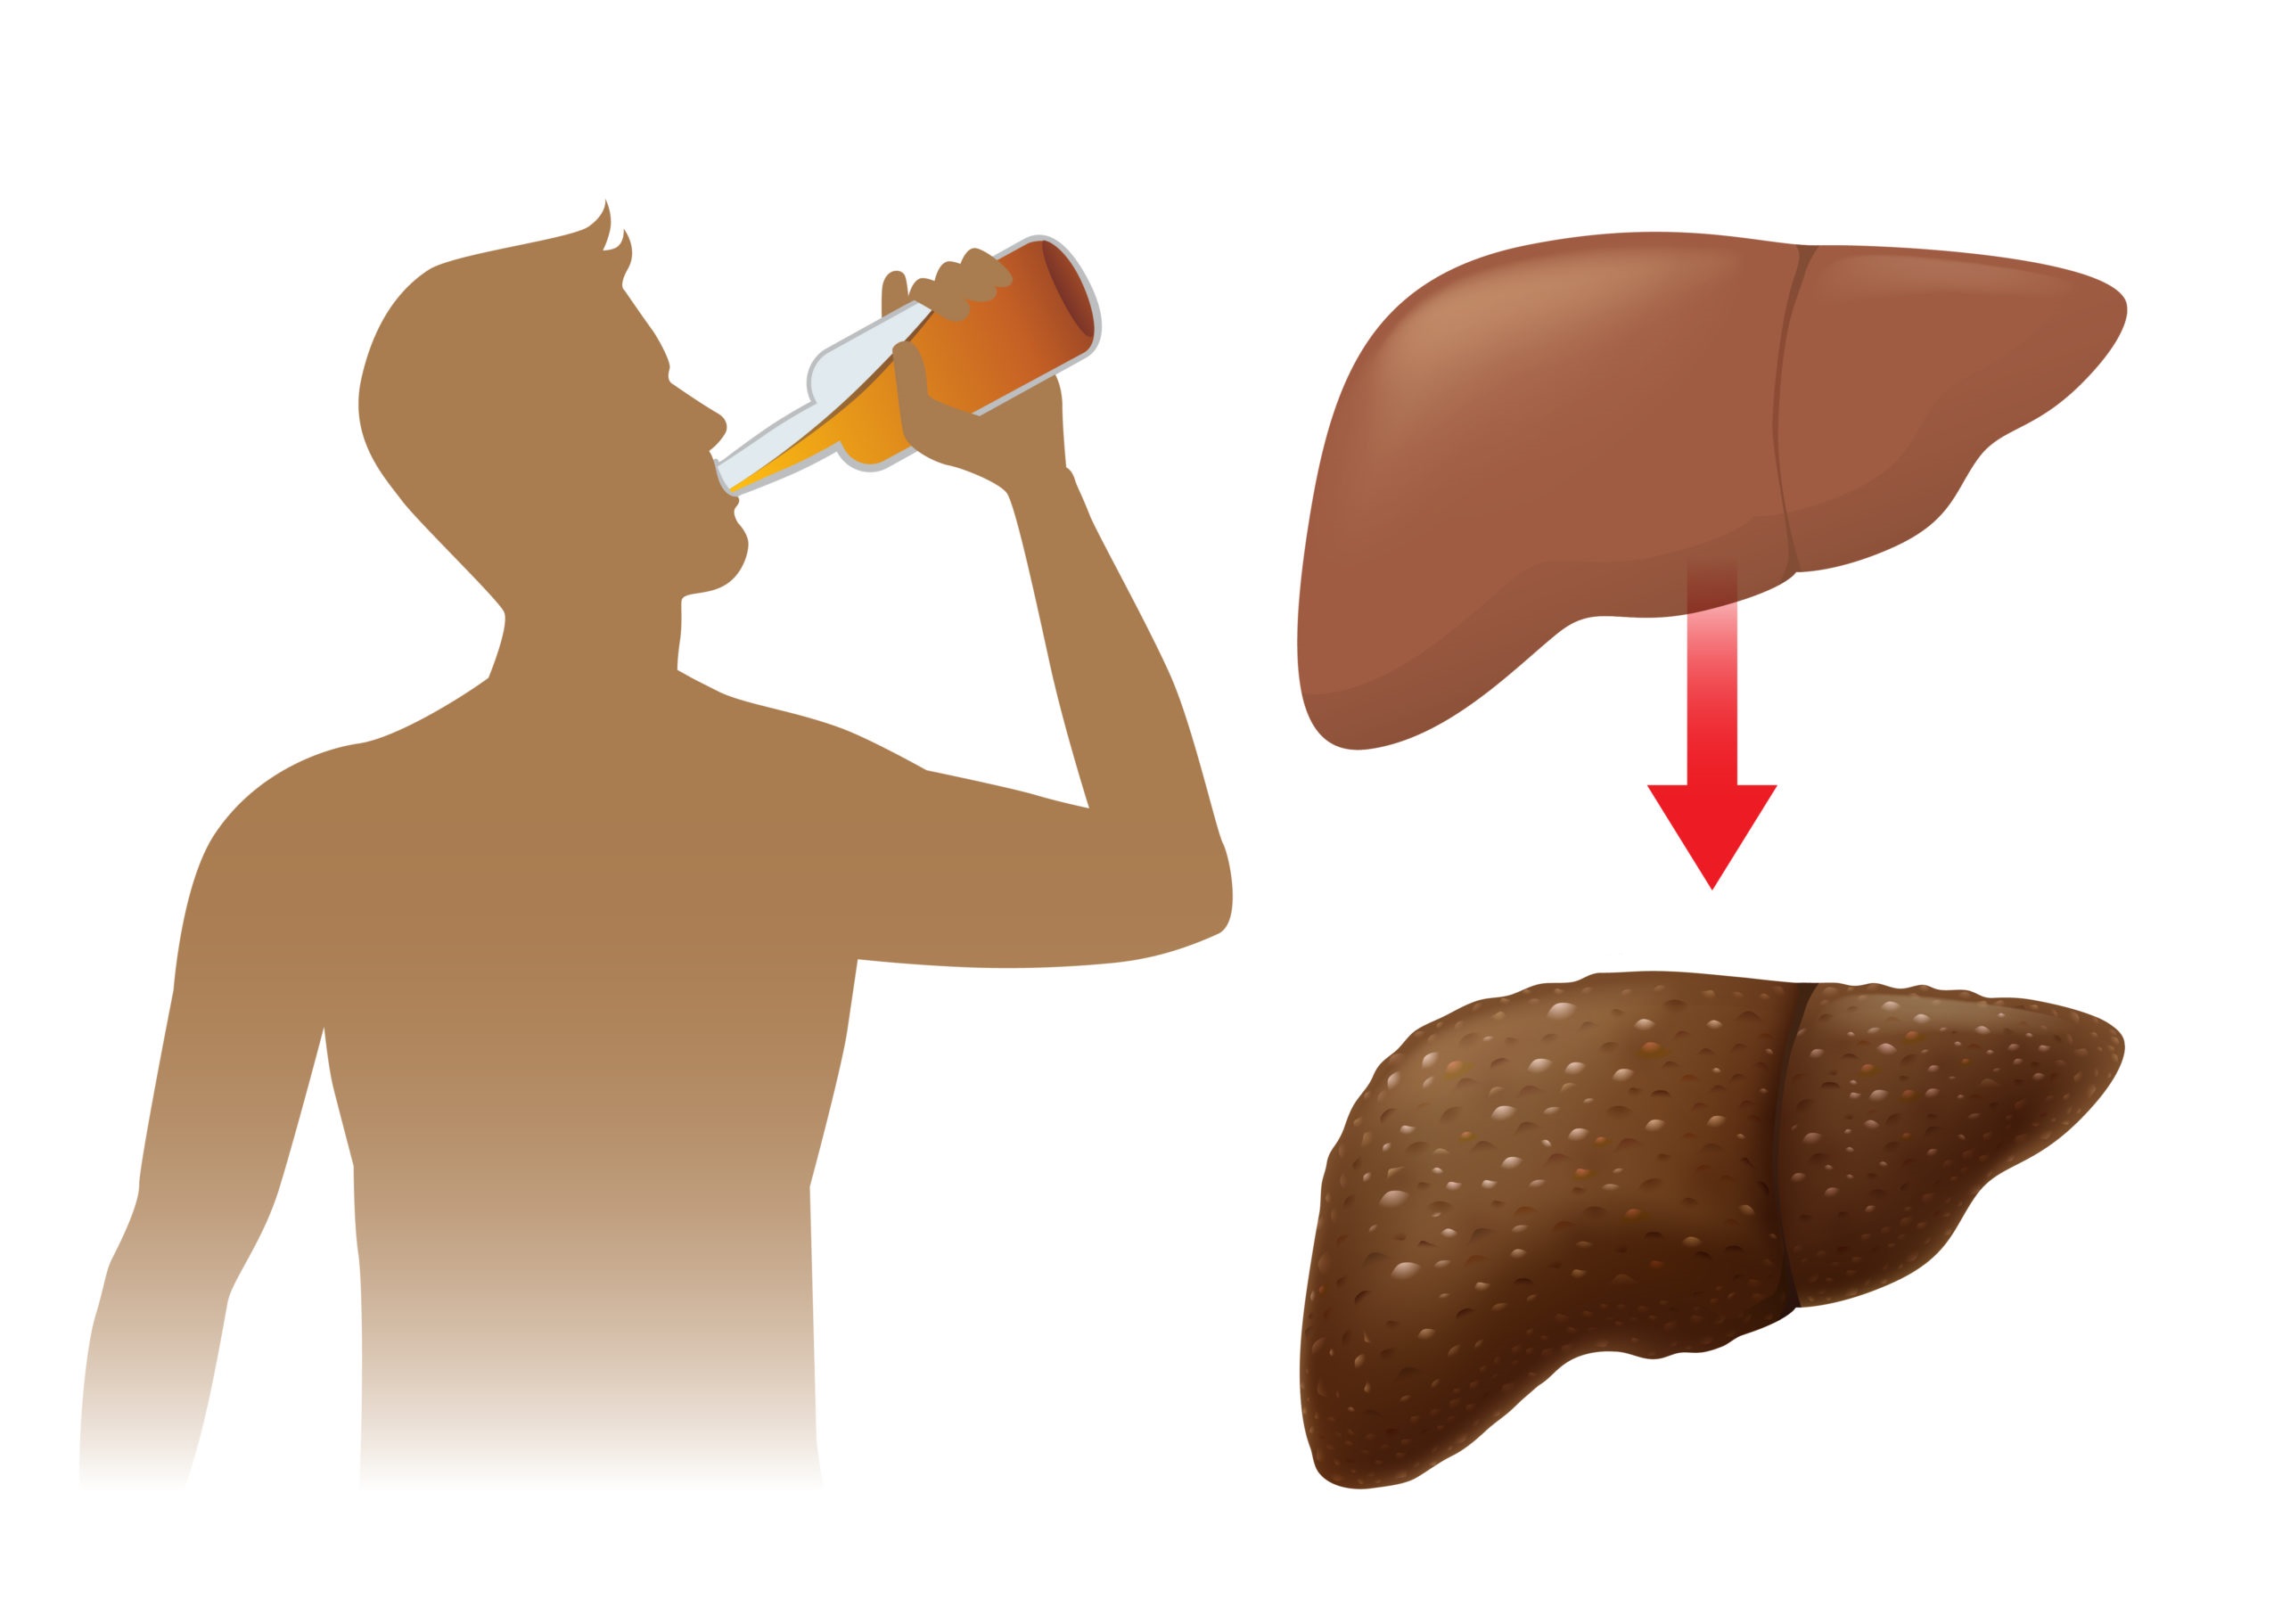

بیماری کبد چرب الکلی

در مورد افرادی که بیش از اندازه مصرف الکل دارند، می توان گفت که این دسته افراد مستعد مبتلا شدن به بیماری کبد چرب الکلی هستند. کبد با تجزیه کردن الکل در بدن می تواند در پس این اتفاق مواد مضر تولید کند که مجموعه این اعمال باعث ایجاد التهاب در کبد و آسیب سلول های کبدی می شود. مرحله ای که ذکر شد، اولین قسمت از بیماری کبدی بر اثر مصرف الکل است و ممکن است فرد بتواند با متوقف کردن مصرف الکل روند آن را معکوس کند و به ریکاوری و بازسازی کبد کمک کند. در غیر این صورت بیماری کبد چرب الکلی می تواند به هپاتیت الکلی یا سیروز تبدیل شود.

مصرف الکل جزء جدا نشدنی از عوامل افزایش خطر ابتلا به کبد چرب است و همانطور که گفته شد، کبد الکل را در خود تجزیه کرده و آن را از بدن خارج می کند. این تجزیه کردن باعث می شود که سموم مضری در بدن آزاد شود و به سلول های کبد آسیب وارد کند.

در بدن افرادی که مبتلا به کبد چرب الکلی هستند، امکان این وجود دارد که با عدم مصرف الکل بتوانند آسیب و التهاب کبد را متوقف کرده یا از بدتر شدن وضعیت آن جلوگیری کنند، اما این عمل در مرحله سیروز کبدی نمی تواند کارساز باشد و روند را معکوس کند و کبد را بهبود ببخشد.

مصرف الکل علت کبد چرب و درمان آن، مصرف نکردن الکل است!

ممکن است ترک الکل برای افراد معتاد به مواد الکلی بسیار کار سختی باشد، ولی این روند می تواند با کمک گرفتن از پزشک متخصص در مورد نحوه انجام این کار به روشی ایمن و حمایت شده، کار را تا حدودی راحت تر کند. افرادی که در مرحله ترک الکل و عوارض ناشی از NASH یا استئاتو هپاتیت غیر الکلی و بیماری کبد چرب الکلی هستند، باید خاطر نشان شوند که در معرض خطر ابتلا به سیروز یا نارسایی کبد هستند!